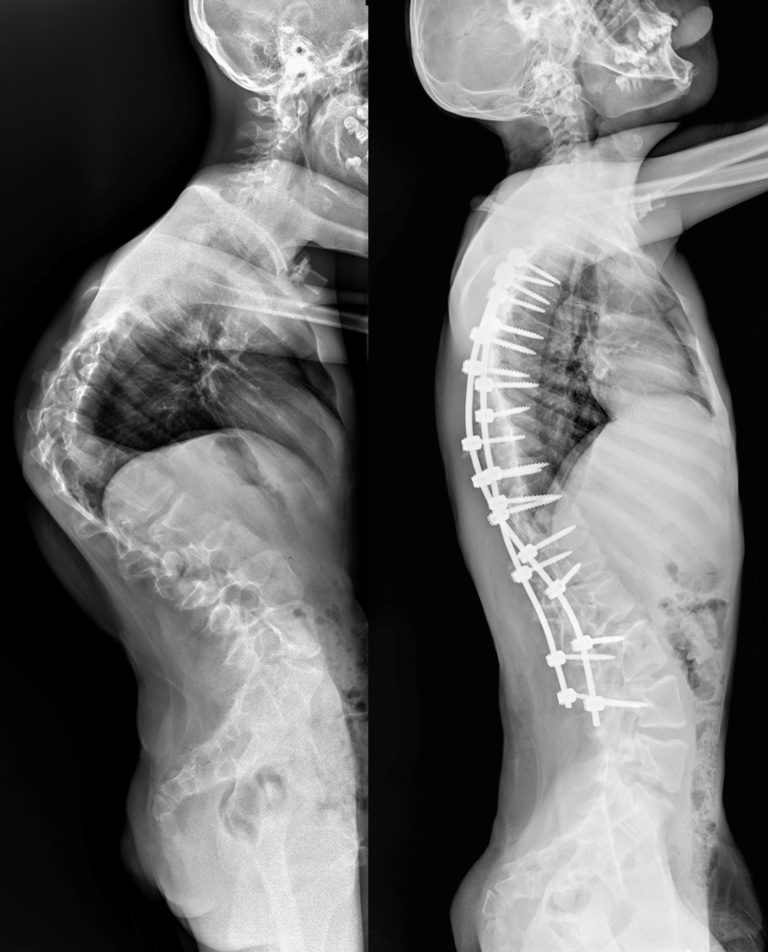

Врачи отделения травматологии и ортопедии РДКБ РНИМУ им. Н.И. Пирогова Минздрава России провели успешную операцию по коррекции кифосколиоза у пациента с синдромом Протея. Хирургическое вмешательство длилось более семи часов и было технически сложным: кифотическая деформация грудного отдела позвоночника составляла более 110 градусов, а комбинированная сколиотическая — по 90 градусов в грудном и поясничном отделах. Благодаря слаженной работе опытной команде хирургов удалось добиться существенной коррекции и обеспечить пациенту достойное качество жизни в будущем. По словам врачей, мальчик даже сможет заниматься своим любимым делом — кататься на велосипеде.

«К нам он поступил с уже существенным искривлением позвоночника, — отмечает Андрей Андреевич. — Кифотическая деформация грудного отдела составляла более 100 градусов, а сколиотическая — более 90 градусов в грудном и поясничном отделах. Отмечались нарушения походки, а совокупность этих и других проблем пациента, связанных с основным диагнозом, сильно влияла на его качество жизни».

«Основой вмешательства стала стандартная методика, — объяснил Андрей Андреевич. — Дорсальным доступом мы установили транспедикулярные винты (через ножки дуг в тела позвонков), затем при помощи специальных корригирующих маневров постепенно привели деформацию в оптимальное положение и зафиксировали стержнями».

Установленная металлоконструкция получилась достаточно протяжённой: от третьего грудного (Т3) по четвертый поясничный (L4) позвонок. Хирурги постарались сохранить подвижность двух сегментов в нижнепоясничном отделе, чтобы уменьшить степень ограниченности физических возможностей пациента в будущем.

После операции Мурат быстро активизировался и восстанавливался. Хирургам удалось добиться невероятных результатов в коррекции: угол кифотической деформации был снижен до 60 градусов (практически вдвое), а сколиотических — до 40-50 градусов, обеспечен удовлетворительный баланс позвоночника в сагиттальной и фронтальной плоскостях.